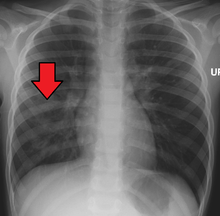

A chest X-ray showing a very prominent wedge-shape area of airspace consolidation in the right lung characteristic of bacterial pneumonia. | |

A chest radiograph is frequently used in diagnosis.[19] In people with mild disease, imaging is needed only in those with potential complications, those not having improved with treatment, or those in which the cause is uncertain.[19][48] If a person is sufficiently sick to require hospitalization, a chest radiograph is recommended.[48] Findings do not always match the severity of disease and do not reliably separate between bacterial infection and viral infection.[19]

X-ray presentations of pneumonia may be classified as lobar pneumonia, bronchopneumonia (also known as lobular pneumonia), and interstitial pneumonia.[51] Bacterial, community-acquired pneumonia classically show lung consolidation of one lung segmental lobe, which is known as lobar pneumonia.[29] However, findings may vary, and other patterns are common in other types of pneumonia.[29] Aspiration pneumonia may present with bilateral opacities primarily in the bases of the lungs and on the right side.[29] Radiographs of viral pneumonia may appear normal, appear hyper-inflated, have bilateral patchy areas, or present similar to bacterial pneumonia with lobar consolidation.[29] Radiologic findings may not be present in the early stages of the disease, especially in the presence of dehydration, or may be difficult to be interpreted in the obese or those with a history of lung disease.[20] A CT scan can give additional information in indeterminate cases.[29]